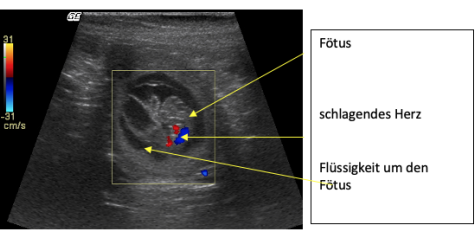

Ultraschallbild Trächtigkeit Hündin

Der kleine Fötus ist sichtbar in einer flüssigkeitsgefüllten Kammer in der Gebärmutter. Bei der Hündin hat der Uterus zwei Hörner und in jedem können sich ein bis mehrere Föten befinden. Dieser Fötus lebt, die Herzaktivität kann Mittels Doppler-Technik (‘farbiger Ultraschall’) visualisiert werden. Diese Hündin hat fünf gesunde Welpen zur Welt gebracht.